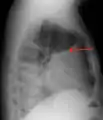

Pleural effusion Anteroposterior Chest X-ray of a pleural effusion. The A arrow shows fluid layering in the right pleural cavity. The B arrow shows the normal width of the lung in the cavity

A pleural effusion appears as an area of whiteness on a standard posteroanterior chest X-ray.[12] Normally, the space between the visceral pleura and the parietal pleura cannot be seen. A pleural effusion infiltrates the space between these layers. Because the pleural effusion has a density similar to water, it can be seen on radiographs. Since the effusion has greater density than the rest of the lung, it gravitates towards the lower portions of the pleural cavity. The pleural effusion behaves according to basic fluid dynamics, conforming to the shape of pleural space, which is determined by the lung and chest wall. If the pleural space contains both air and fluid, then an air-fluid level that is horizontal will be present, instead of conforming to the lung space.[13] Chest radiographs in the lateral decubitus position (with the patient lying on the side of the pleural effusion) are more sensitive and can detect as little as 50 mL of fluid. Between 250 and 600mL of fluid must be present before upright chest X-rays can detect a pleural effusion (e.g., blunted costophrenic angles).[14]